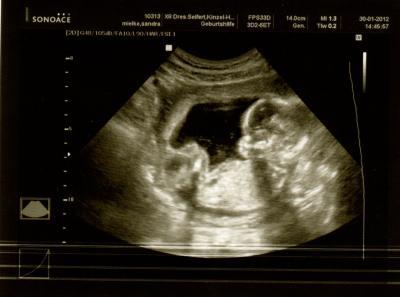

Hier noch mal das "Beweis" Foto- dass es wahrscheinlich ein Junge wird- die Ärztin meinte nächstes mal wird mans deutlicher sehen können

Bild zu